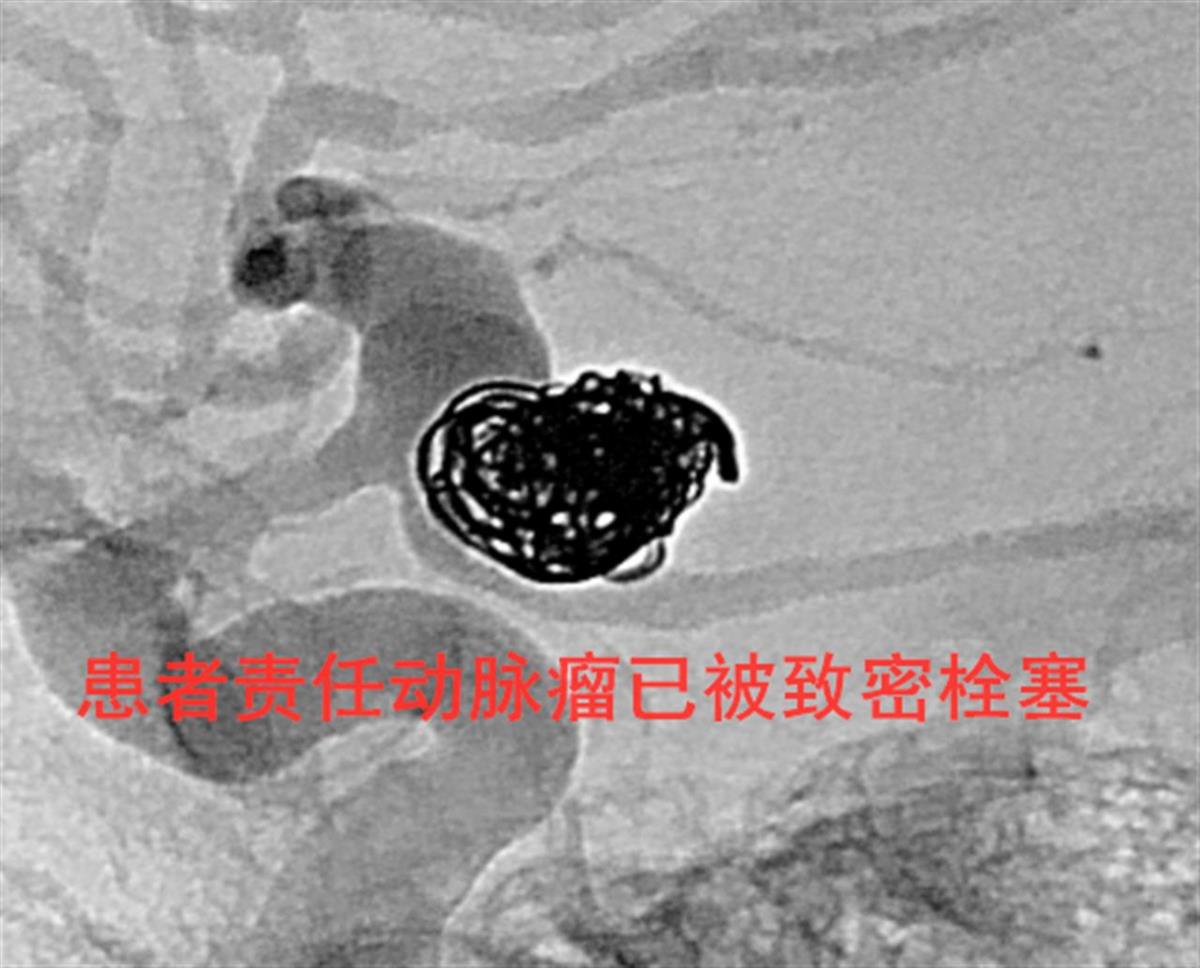

鉴于马先生入院时呈昏睡状态、舌后坠严重,且合并较重的神经系统功能障碍,医院立即启动绿色通道,迅速完善急诊影像检查,确诊马先生是动脉瘤破裂引发蛛网膜下腔出血。时间就是生命,该院脑血管病中心主任潘力教授立即组织介入团队,为他紧急开展急诊颅内动脉瘤栓塞术。凭借丰富的动脉瘤栓塞手术经验,潘力带领脑血管介入团队精准锁定动脉瘤——患者左侧颈内动脉C7段远端的夹层动脉瘤,同时克服瘤颈较宽、破裂出血量大、术后长期双抗风险较高等重重困境,为他实施了术中双微导管联合栓塞,及术后腰椎穿刺术。